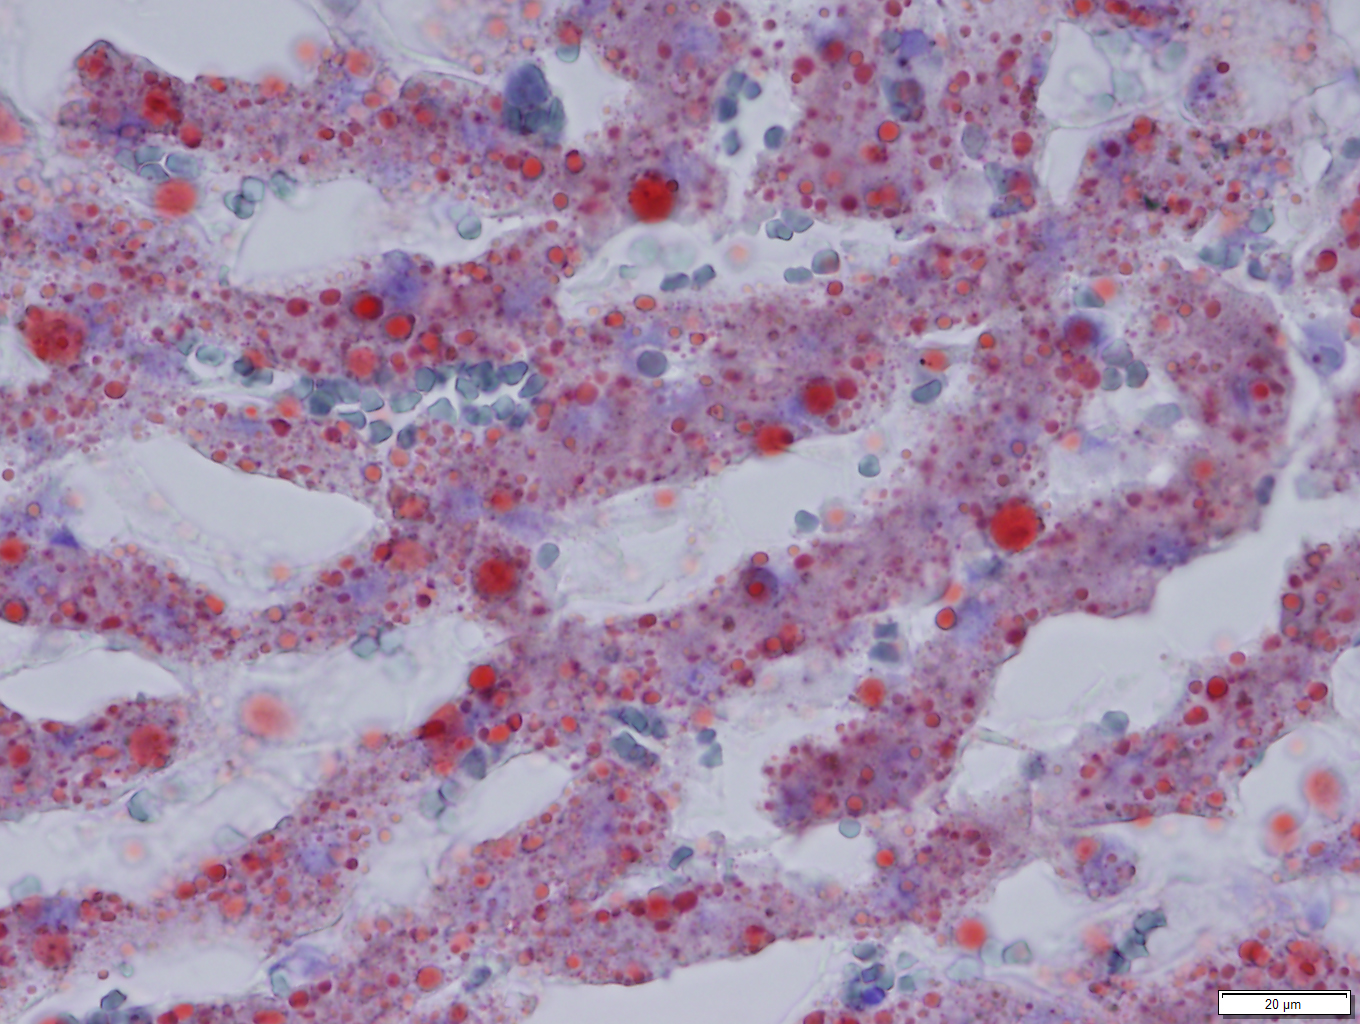

Microscopic Description:

Liver: Diffusely, hepatocytes are moderately swollen and contain numerous small (~1µm) discrete to coalescing cytoplasmic vacuoles (microvesicular hepatopathy). Nuclei remain centrally located. Within the centrilobular interstitium, hepatocytes are occasionally individualized, rounded, shrunken, and/or hypereosinophilic with karyolysis (necrosis). There is mild, patchy periportal hemorrhage.

Special stains:

Osmium tetroxide post-fixation revealed prominent staining of microvesicular lesions, confirming the vacuoles as lipid droplets.

Oil Red O revealed prominent staining of microvesicular lesions, again confirming the vacuoles as lipid droplets.

Contributor’s Morphologic Diagnoses:

Liver: Microvesicular hepatopathy, moderate, acute, diffuse, with mild centrilobular hepatocellular necrosis.